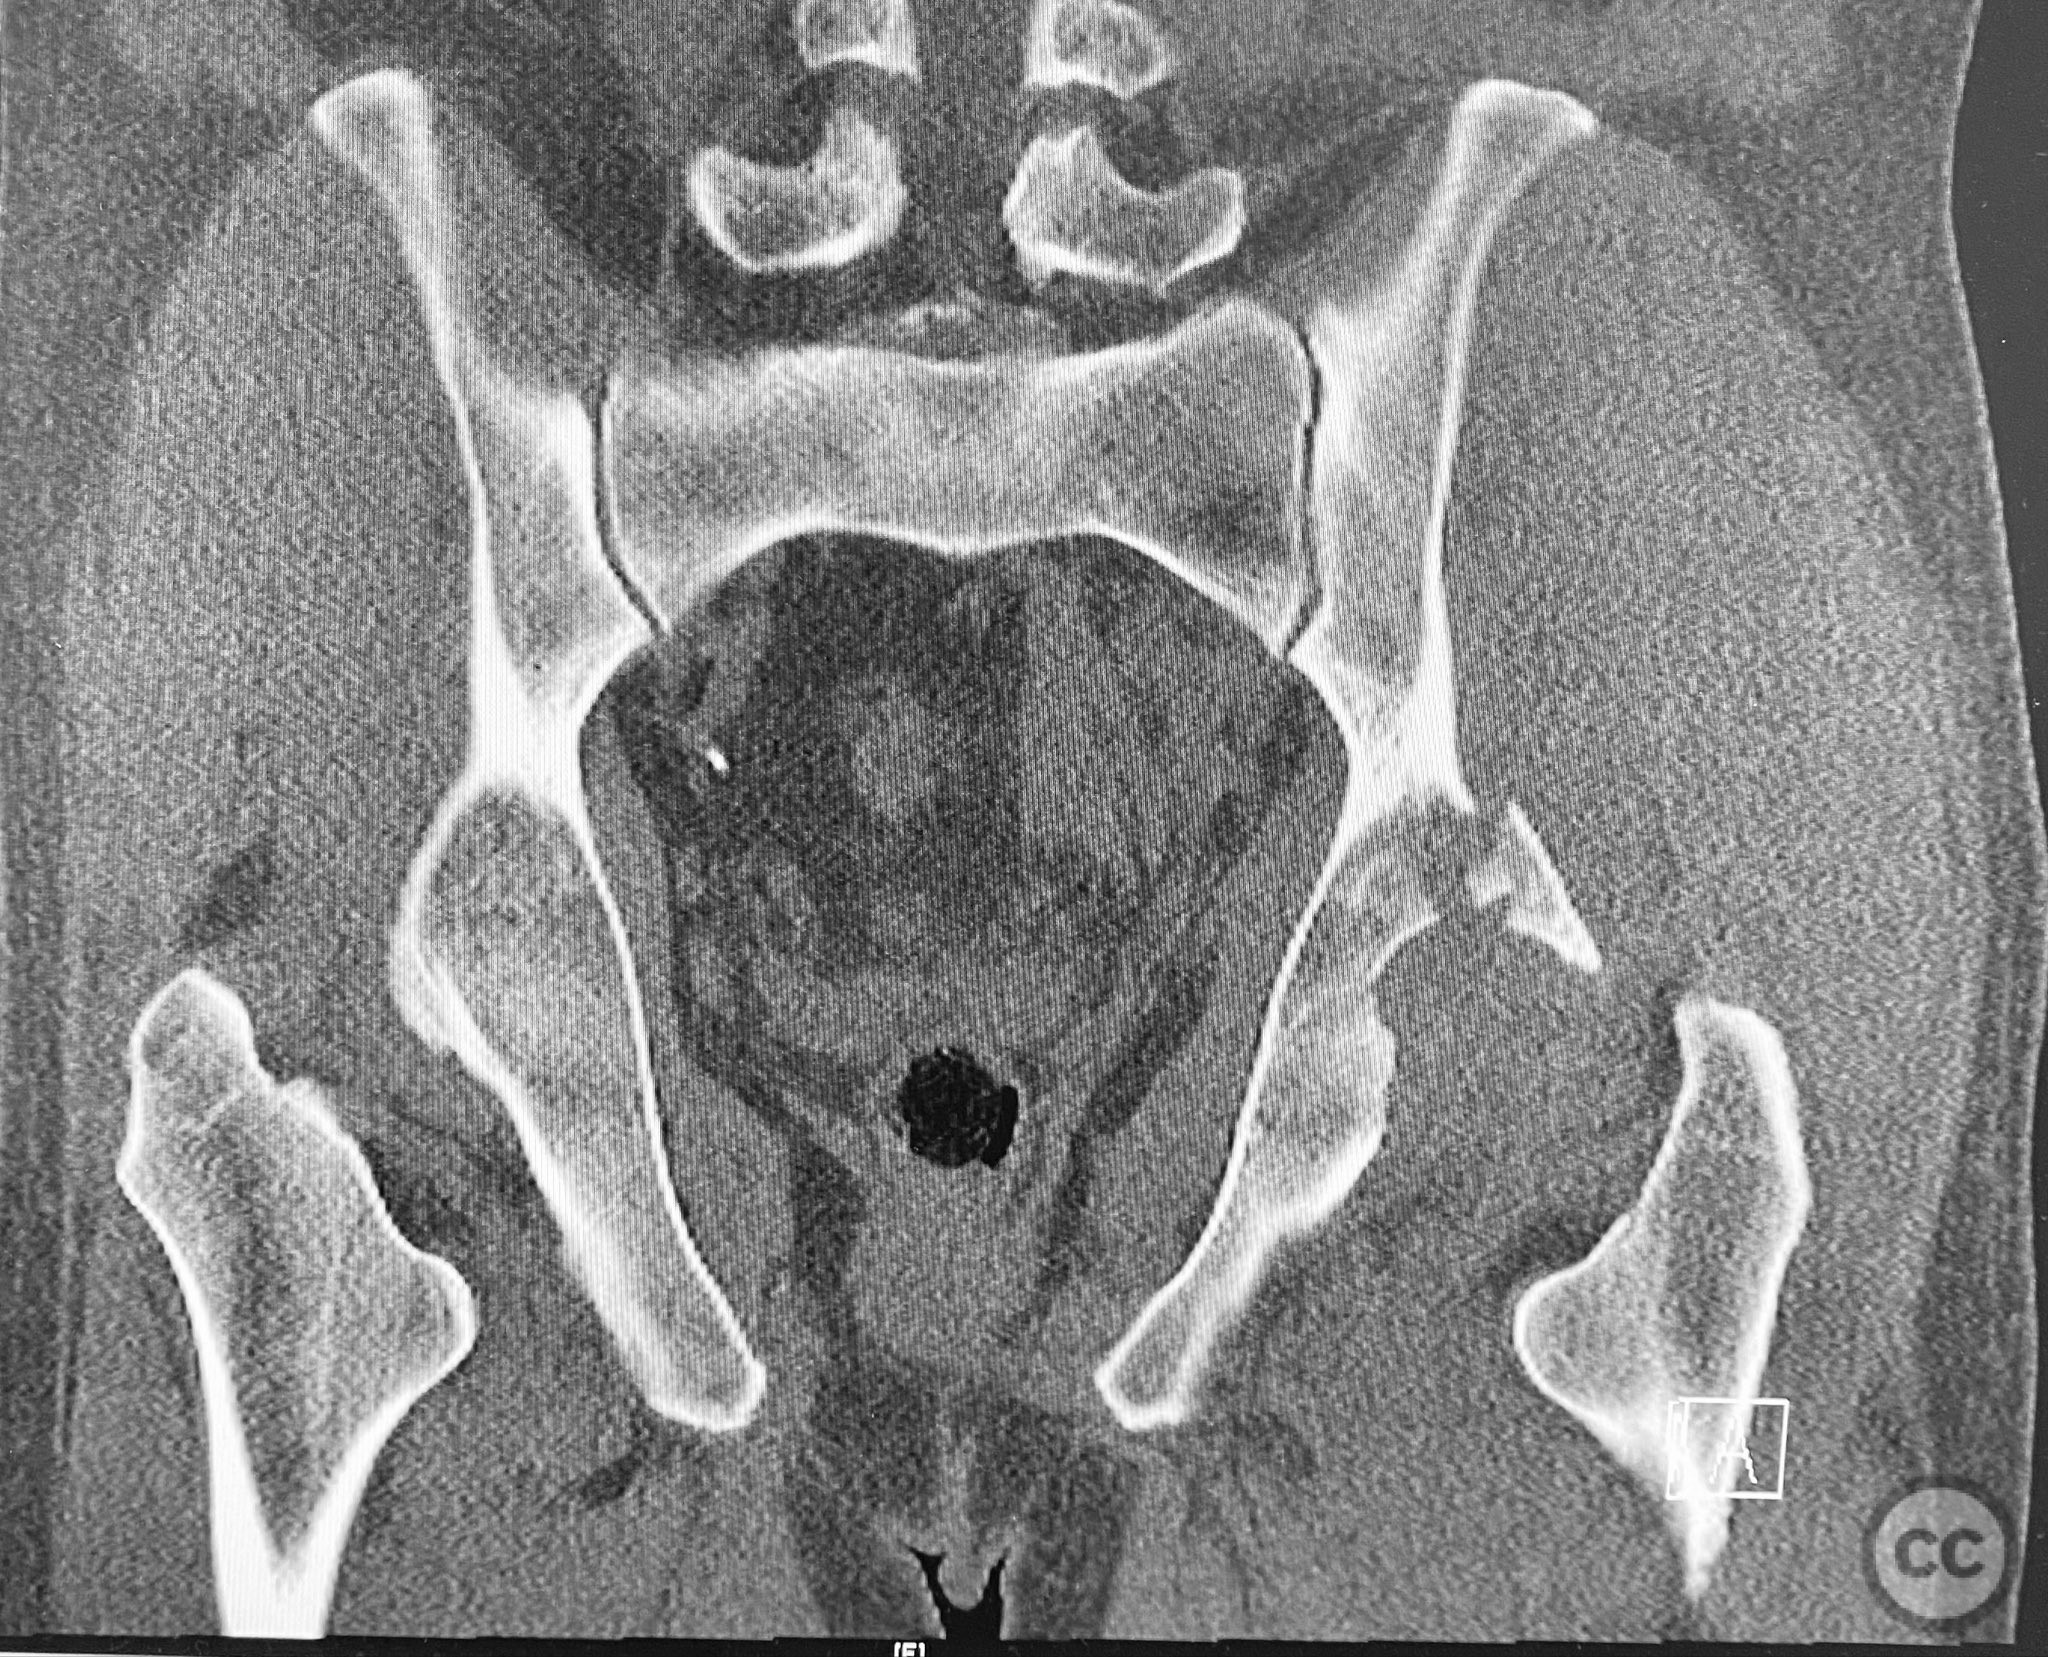

Clinical and radiological findings:  A patient presented with a seemingly non-comminuted, wide, and long posterior wall (PW) acetabular fracture fragment. Axial computed tomography (CT) images demonstrated the thickness of the PW fragment, the articular surface, and multiple areas of subchondral impaction. Preoperative planning identified the size, location, and depth of the impaction zones, as well as an essentially nondisplaced transverse acetabular fracture line, which was not readily apparent on initial imaging. No significant displacement of the transverse component was noted. The AO/OTA classification is 62-B1.3 (posterior wall and transverse acetabular fracture).